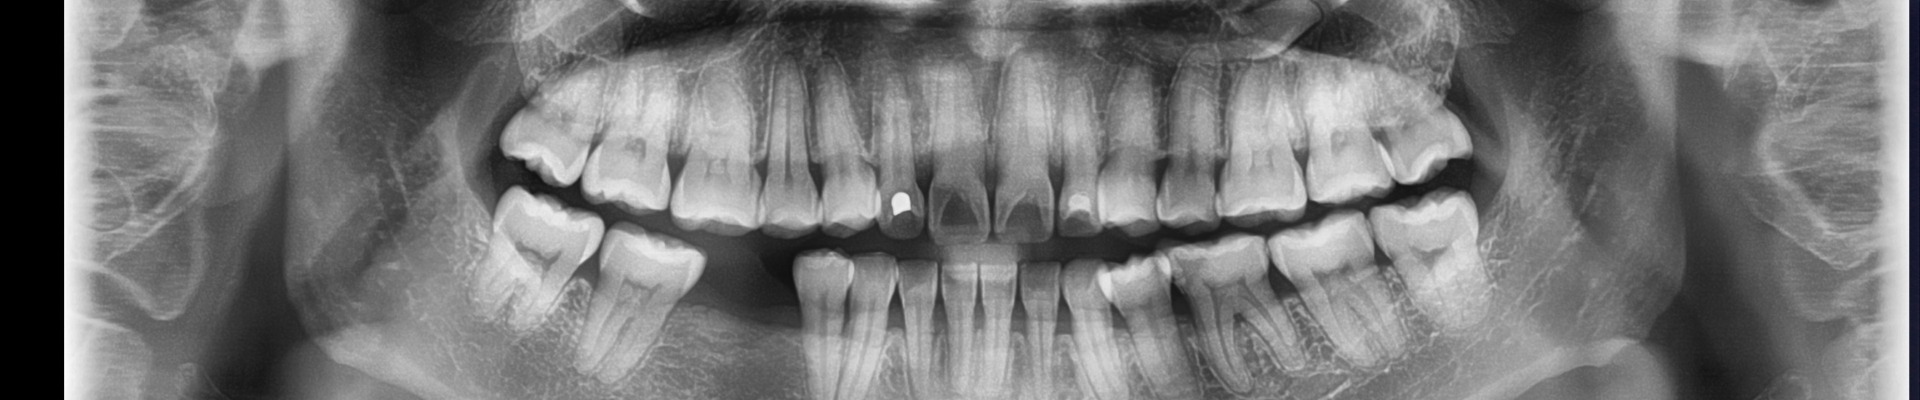

Ψηφιακή Πανοραμική Ακτινογραφία

Η πανοραμική ακτινογραφία αποτελεί την πλέον χρήσιμη ακτινογραφική εξέταση στην καθημερινή οδοντιατρική πράξη για τον πλήρη έλεγχο του οδοντικού φραγμού. Είναι η μοναδική ακτινογραφική τεχνική που δίνει τη δυνατότητα στον Οδοντίατρο να δει σε μια εικόνα όλα τα δόντια και τα οστά τόσο της άνω και της κάτω γνάθου.

Ο τρόπος λήψης είναι απλός και πραγματοποιείται, με μια πλήρη περιστροφή του μηχανήματος γύρω από το κεφάλι του εξεταζόμενου σε χρόνο εξέτασης περίπου 10 δευτερολέπτων. Μεγάλη σημασία έχει η ορθή τοποθέτηση του εξεταζόμενου.